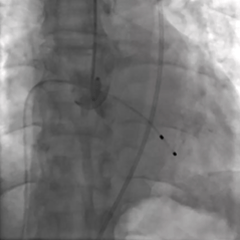

手术过程

造影及超声均可见主动脉瓣大量反流

无窦侧0位起始,最终释放深度满意

多角度评估位置合适,无瓣周漏

瓣膜释放后无位移,锚定牢固